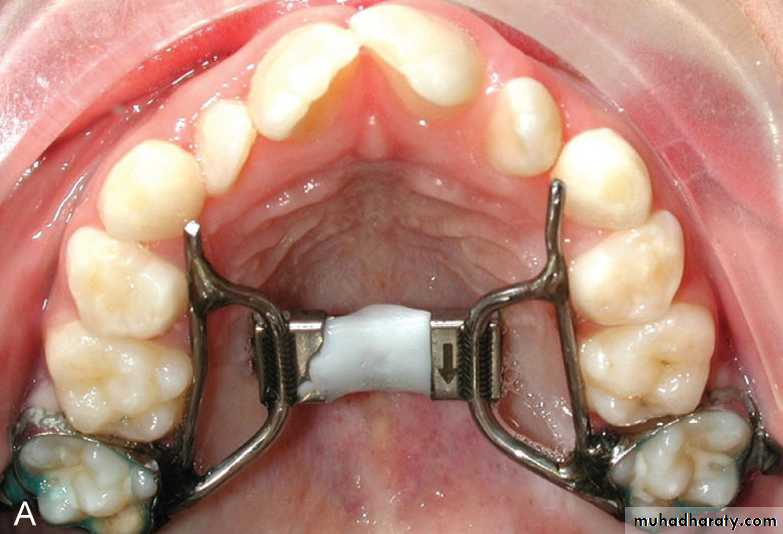

• Lingual arch either of W arch or quad helix design.

Both produce slow expansion and deliver a force of few hundreds grams and produce both skeletal and dental expansion.Expansion of narrow maxilla in late mixed dentition

• W arch and quad helix are reliable and easy to use.

Both are constructed from 0.9 mm stainless steel wire and can be adjusted to produce anterior or posterior expansion.

The lingual wire should contact the teeth involved in crossbite.

The appliance is activated by opening it 3-5 mm wider than passive width.